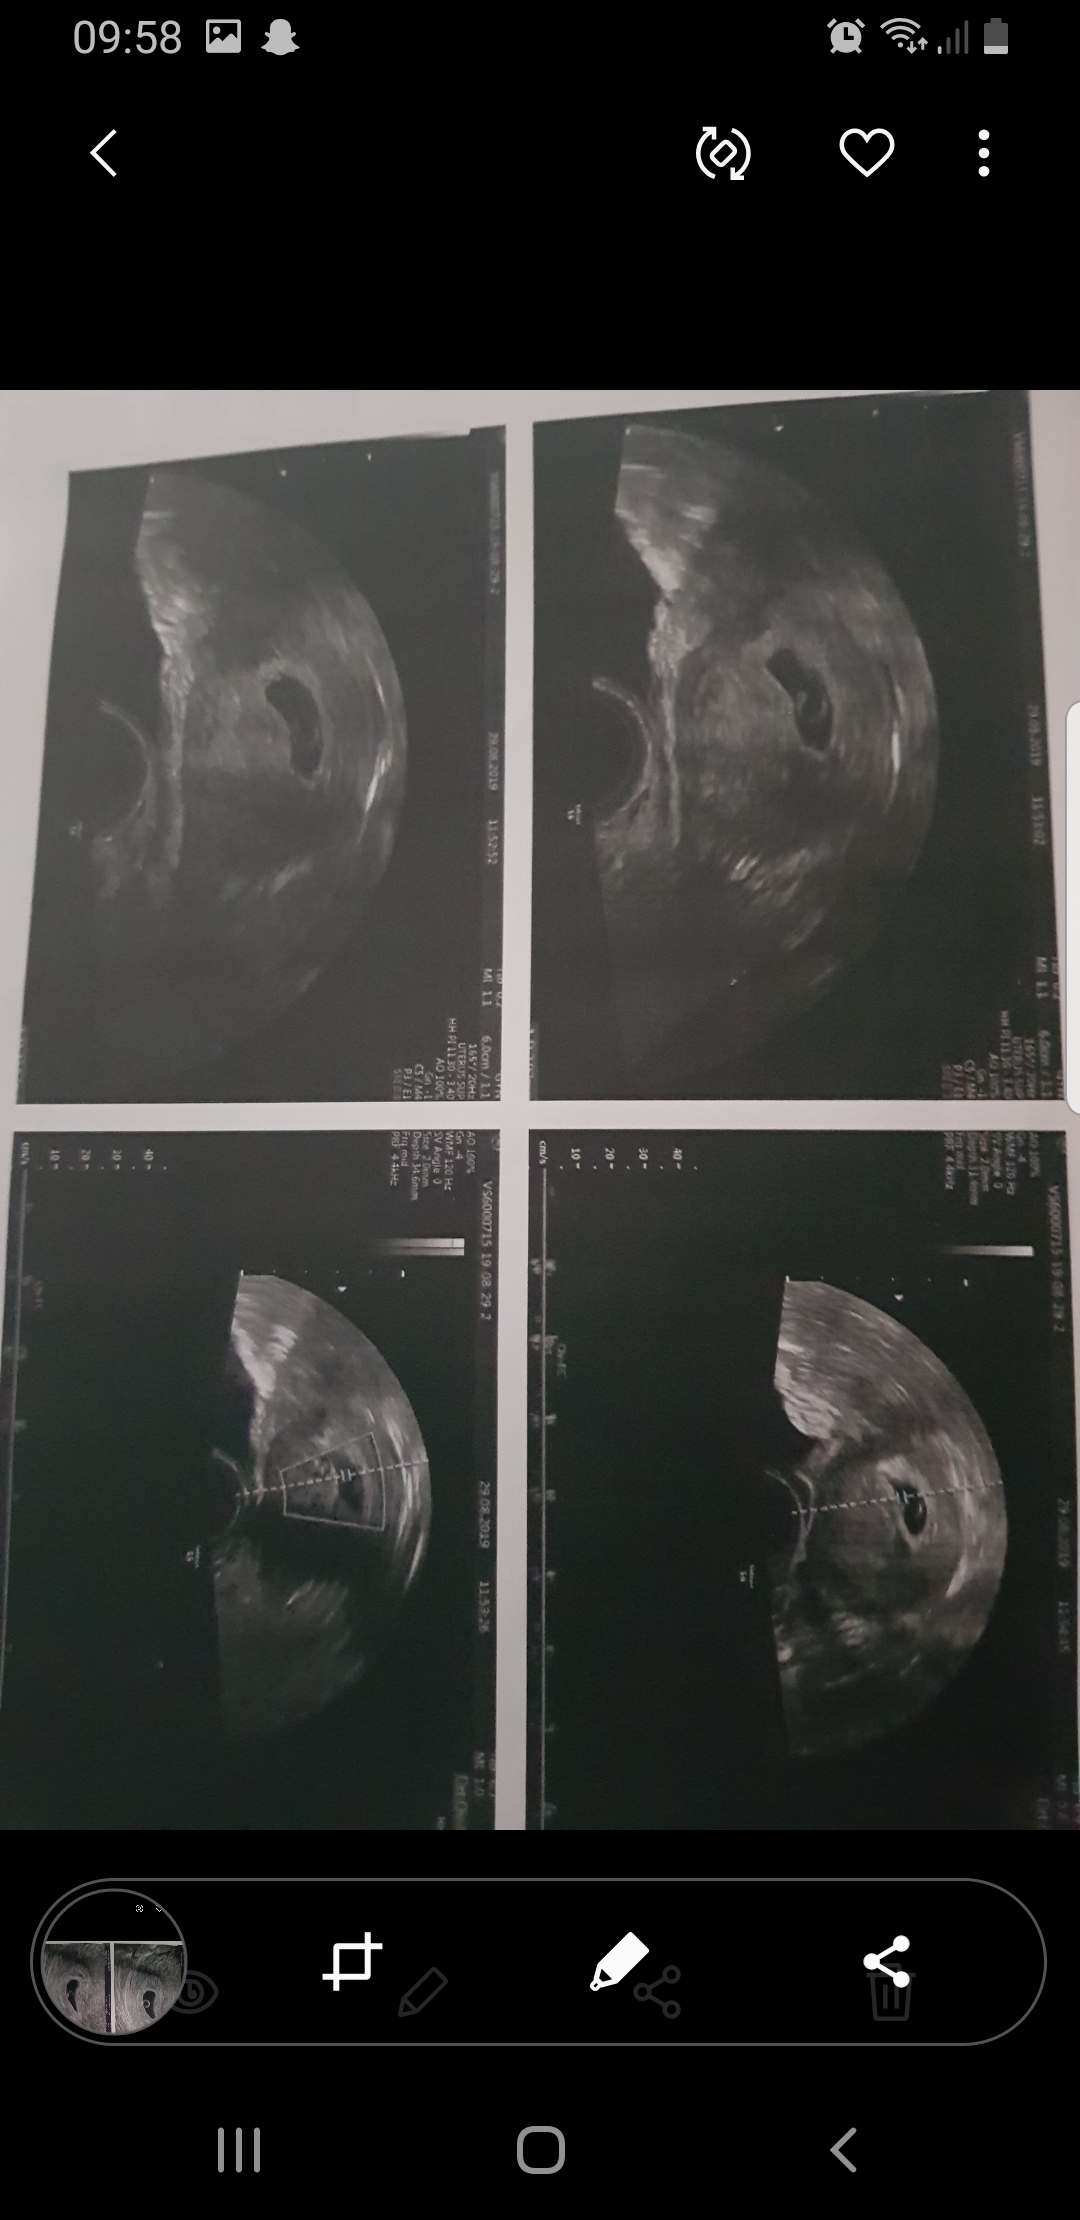

DPO 27, ça correspond à 5sa+6, j'ai pu voir la vésicule vitreline et un truc qui clignotait et qu'on m'a dit être le coeur :) après à ce stade ça se joue à deux/trois jours près je crois.

5sa+6 : 3mm

6sa 4.4 mm

Alors jai eu mon eco comme je tavais dit par ma gynéco. Trop bien embryon de 2.7mm avec un coeur qui bat

Puis 3 jours après. Saignement donc eco de controle a la Pma a 6+1sa. Sac de 20mm, embryon de 3mm coeur qui bat à 118. Pour elle tout est ok. Sauf que depuis je dors plus ni rien.

En 3 jours mon embryon na pas évolué.

Pour la taille, j'avais les mêmes questions que toi. Déjà clairement le fait de faire sur des appareils différents peu jouer, ensuite 3mm à 6sa+1 ne me parait pas du tout choquant de memoire j'etais à 2.9mm à 6sa.